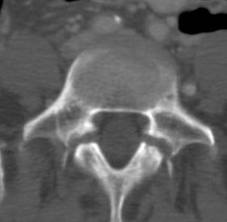

1. A 79-year old man falls sustaining a hyperextension injury to his neck. A lateral radiograph, CT scan and MRI are seen in Figures A through C. On motor examination, he has 3/5 strength in his deltoids, elbow and wrist flexors and extensors. He has 4/5 strength in his hip flexors, knee flexors, extensors, ankle dorsiflexors and plantarflexors. Sensation is preserved in both his upper and lower extremities as well as his sacral segments. Injury to which of the following tracts contributes greatest to his motor function deficits?

FIGURES: A

B

C

DISCUSSION: The clinical scenario describes a patient with central cord syndrome, resulting in an injury to his lateral corticospinal tract. Figures A through C show a spondylytic spine with central narrowing and CSF effacement that is worse at the C4-5 level. The lateral corticospinal tract is the main descending motor tract (Illustration A). Its anatomic position places the upper extermity motor tracts at greater risk than the lower extremity tracts. As such, injury to the lateral corticospinal tract is characterized by upper greater than lower extremity involvement and motor deficits being more pronounced than sensory deficits.